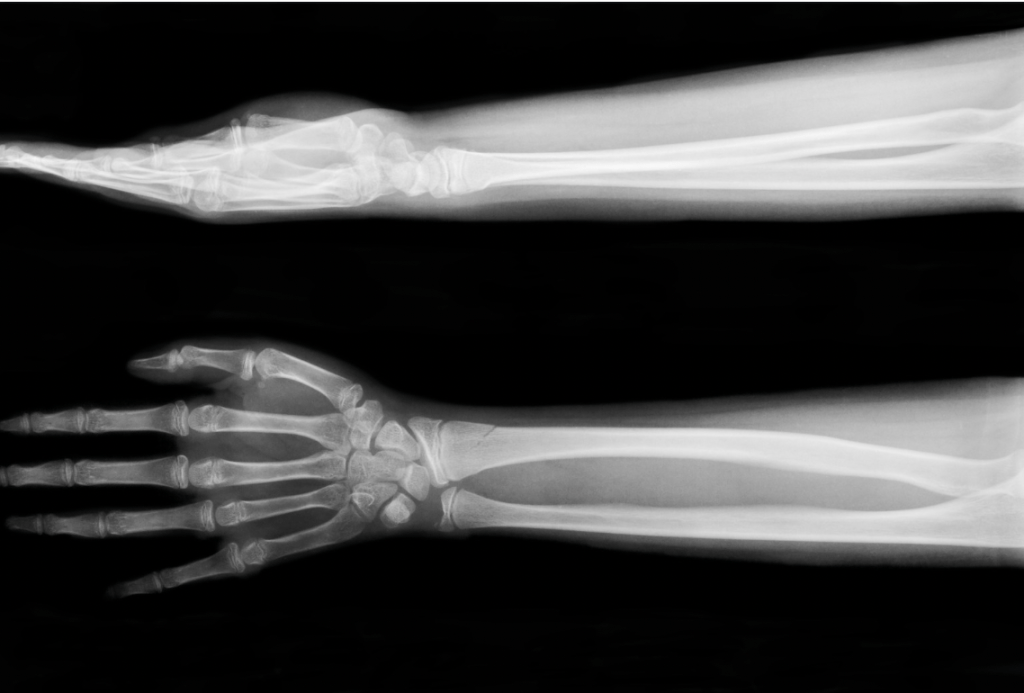

Fractures/Broken Bones

Fractures or broken bones are among the most common injuries in car accidents. The impact of a crash can easily break the bones in the leg, specifically the femur, tibia, and fibula. These injuries can range from minor fractures to severe compound fractures where the bone protrudes through the skin.

Treatment for fractures usually involves resetting and immobilizing the broken bone with a cast or splint. In severe cases, surgery might be necessary to insert metal rods or plates to hold the bone together while it heals.